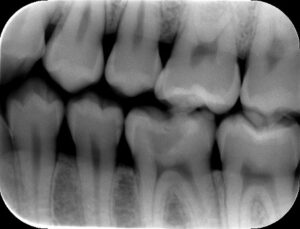

歯に詰めるプラスチックが危ない パート2

1月15日に、奥歯に詰めたプラスチックの周りから虫歯になっている人が非常に多いという話をしました。 今日もそんな患者様がいらっしゃいました。下の写真です。 麻酔をして、プラスチックを外すと、前回のように虫歯が拡がってボロボロというほどではな […] 本文を読む

歯に詰めるプラスチックが危ない

今、歯に詰めたプラスチックの周りから虫歯になっている人が非常に多いです。特に奥歯に詰めた咬み合わせの面のプラスチックが非常に危険です。 どうして、こんな事が起こるのかと言うと、最大の原因は、プラスチックが硬化する時の収縮です。 虫歯の治療は […] 本文を読む